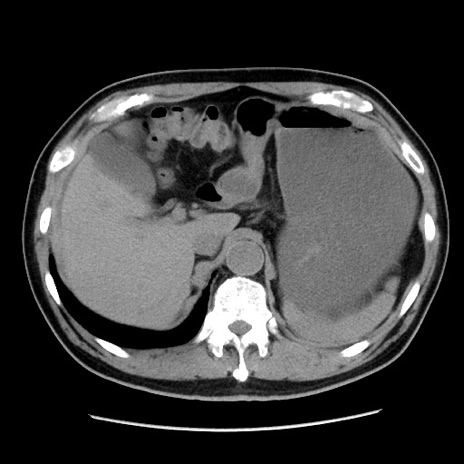

症例16(横断像)

【症例】 70歳代男性

【主訴】 腹痛、嘔吐

【現病歴】 約1ヶ月前より間欠的に腹痛と嘔吐あり、当院消化器内科を受診したところCTで多発する肝臓のLDAを指摘され、精査中であった。以降は消化器症状は安定していたが、2日前より嘔気と腹痛があり、同日より排便・排ガスが消失した。改善認めず、 本日、救急外来を受診した。

【既往歴】 大腸ポリープ切除後。

【身体所見】意識清明・会話良好、BT 36.3℃、BP 127/80mmHg、 P 80bpm、腹部:膨満あり、平坦・軟、上腹部正中および下腹部正中に圧痛あり、反跳痛なし、筋性防御なし。

【データ】WBC 7200、CRP 0.77